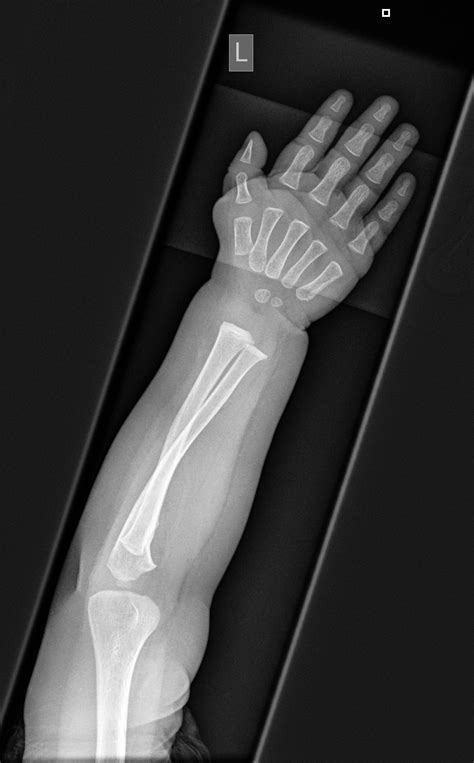

Infant X-ray imaging involves the use of low-dose radiation to produce images of the internal body structures. This technique is particularly useful for diagnosing conditions such as fractures, pneumonia, and congenital anomalies. The process is quick and relatively painless, making it suitable for infants who may be too young to cooperate with more complex diagnostic procedures.

• Early Detection of Fractures: X-rays can quickly identify fractures, which is essential for prompt treatment and recovery.

• Assessment of Congenital Anomalies: X-rays can help identify congenital anomalies, such as heart defects or skeletal abnormalities, which may require immediate medical attention.

Fractures X-rays can identify fractures in bones, which may result from accidents or underlying conditions like osteoporosis.

Congenital Anomalies X-rays can reveal congenital anomalies, such as heart defects or skeletal abnormalities, which may require immediate medical attention.